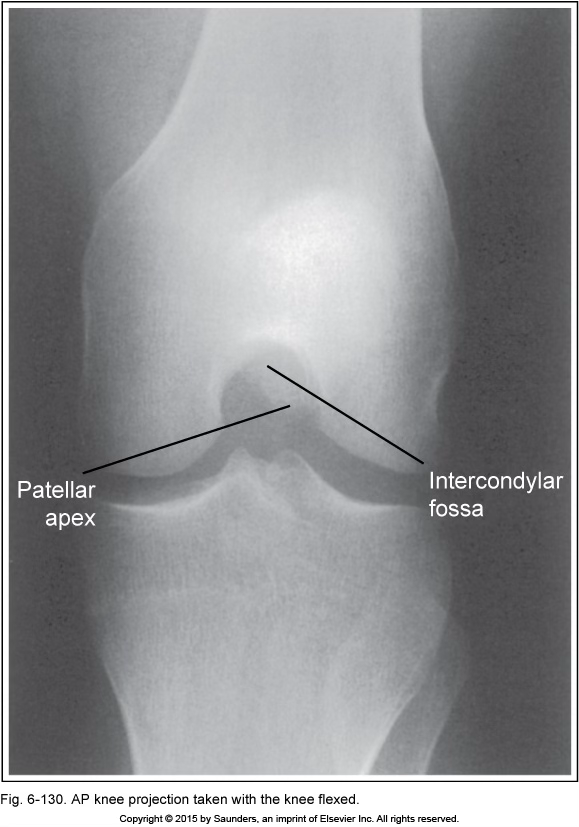

AP knee

knee flexed